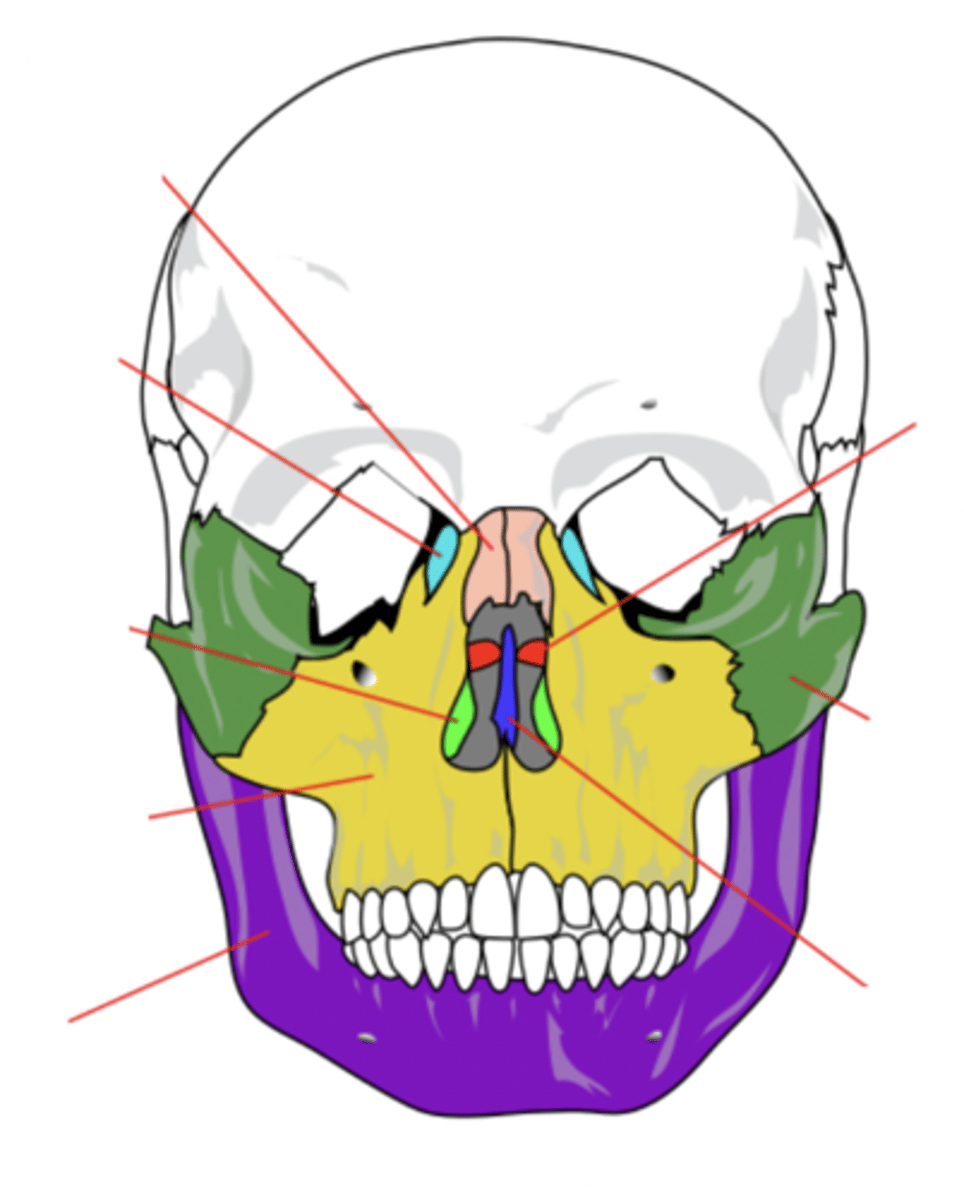

Facial Bones (14)

- Maxilla (2)

- Mandible

- Lacrimal (2)

- Palatine (2)

- Inferior conchae (2)

- Vomer

- Nasal (2)

- Zygomatic (2)

(Many Mammals Like Playing In Very Nice Zoos)

Maxilla Bone (2)

Upper jaw bone (yellow)

Mandible Bone

Lower jaw bone (purple)

Lacrimal Bone (2)

Small fragile bone making up part of the front inner walls of each eye socket and providing room for the passage of the lacrimal ducts (light blue)

Palatine Bone (2)

Bone that forms the hard palate and parts of the nose and orbits (red)

Inferior Conchae Bone (2)

The thin, scroll-like bones that form part of the interior of the nose (light green)

Vomer Bone

Bone that forms the inferior portion of the nasal septum (blue)

Nasal Bone (2)

Bone that forms the bridge of the nose (pink)

Zygomatic Bone (2)

Cheek bone (green)